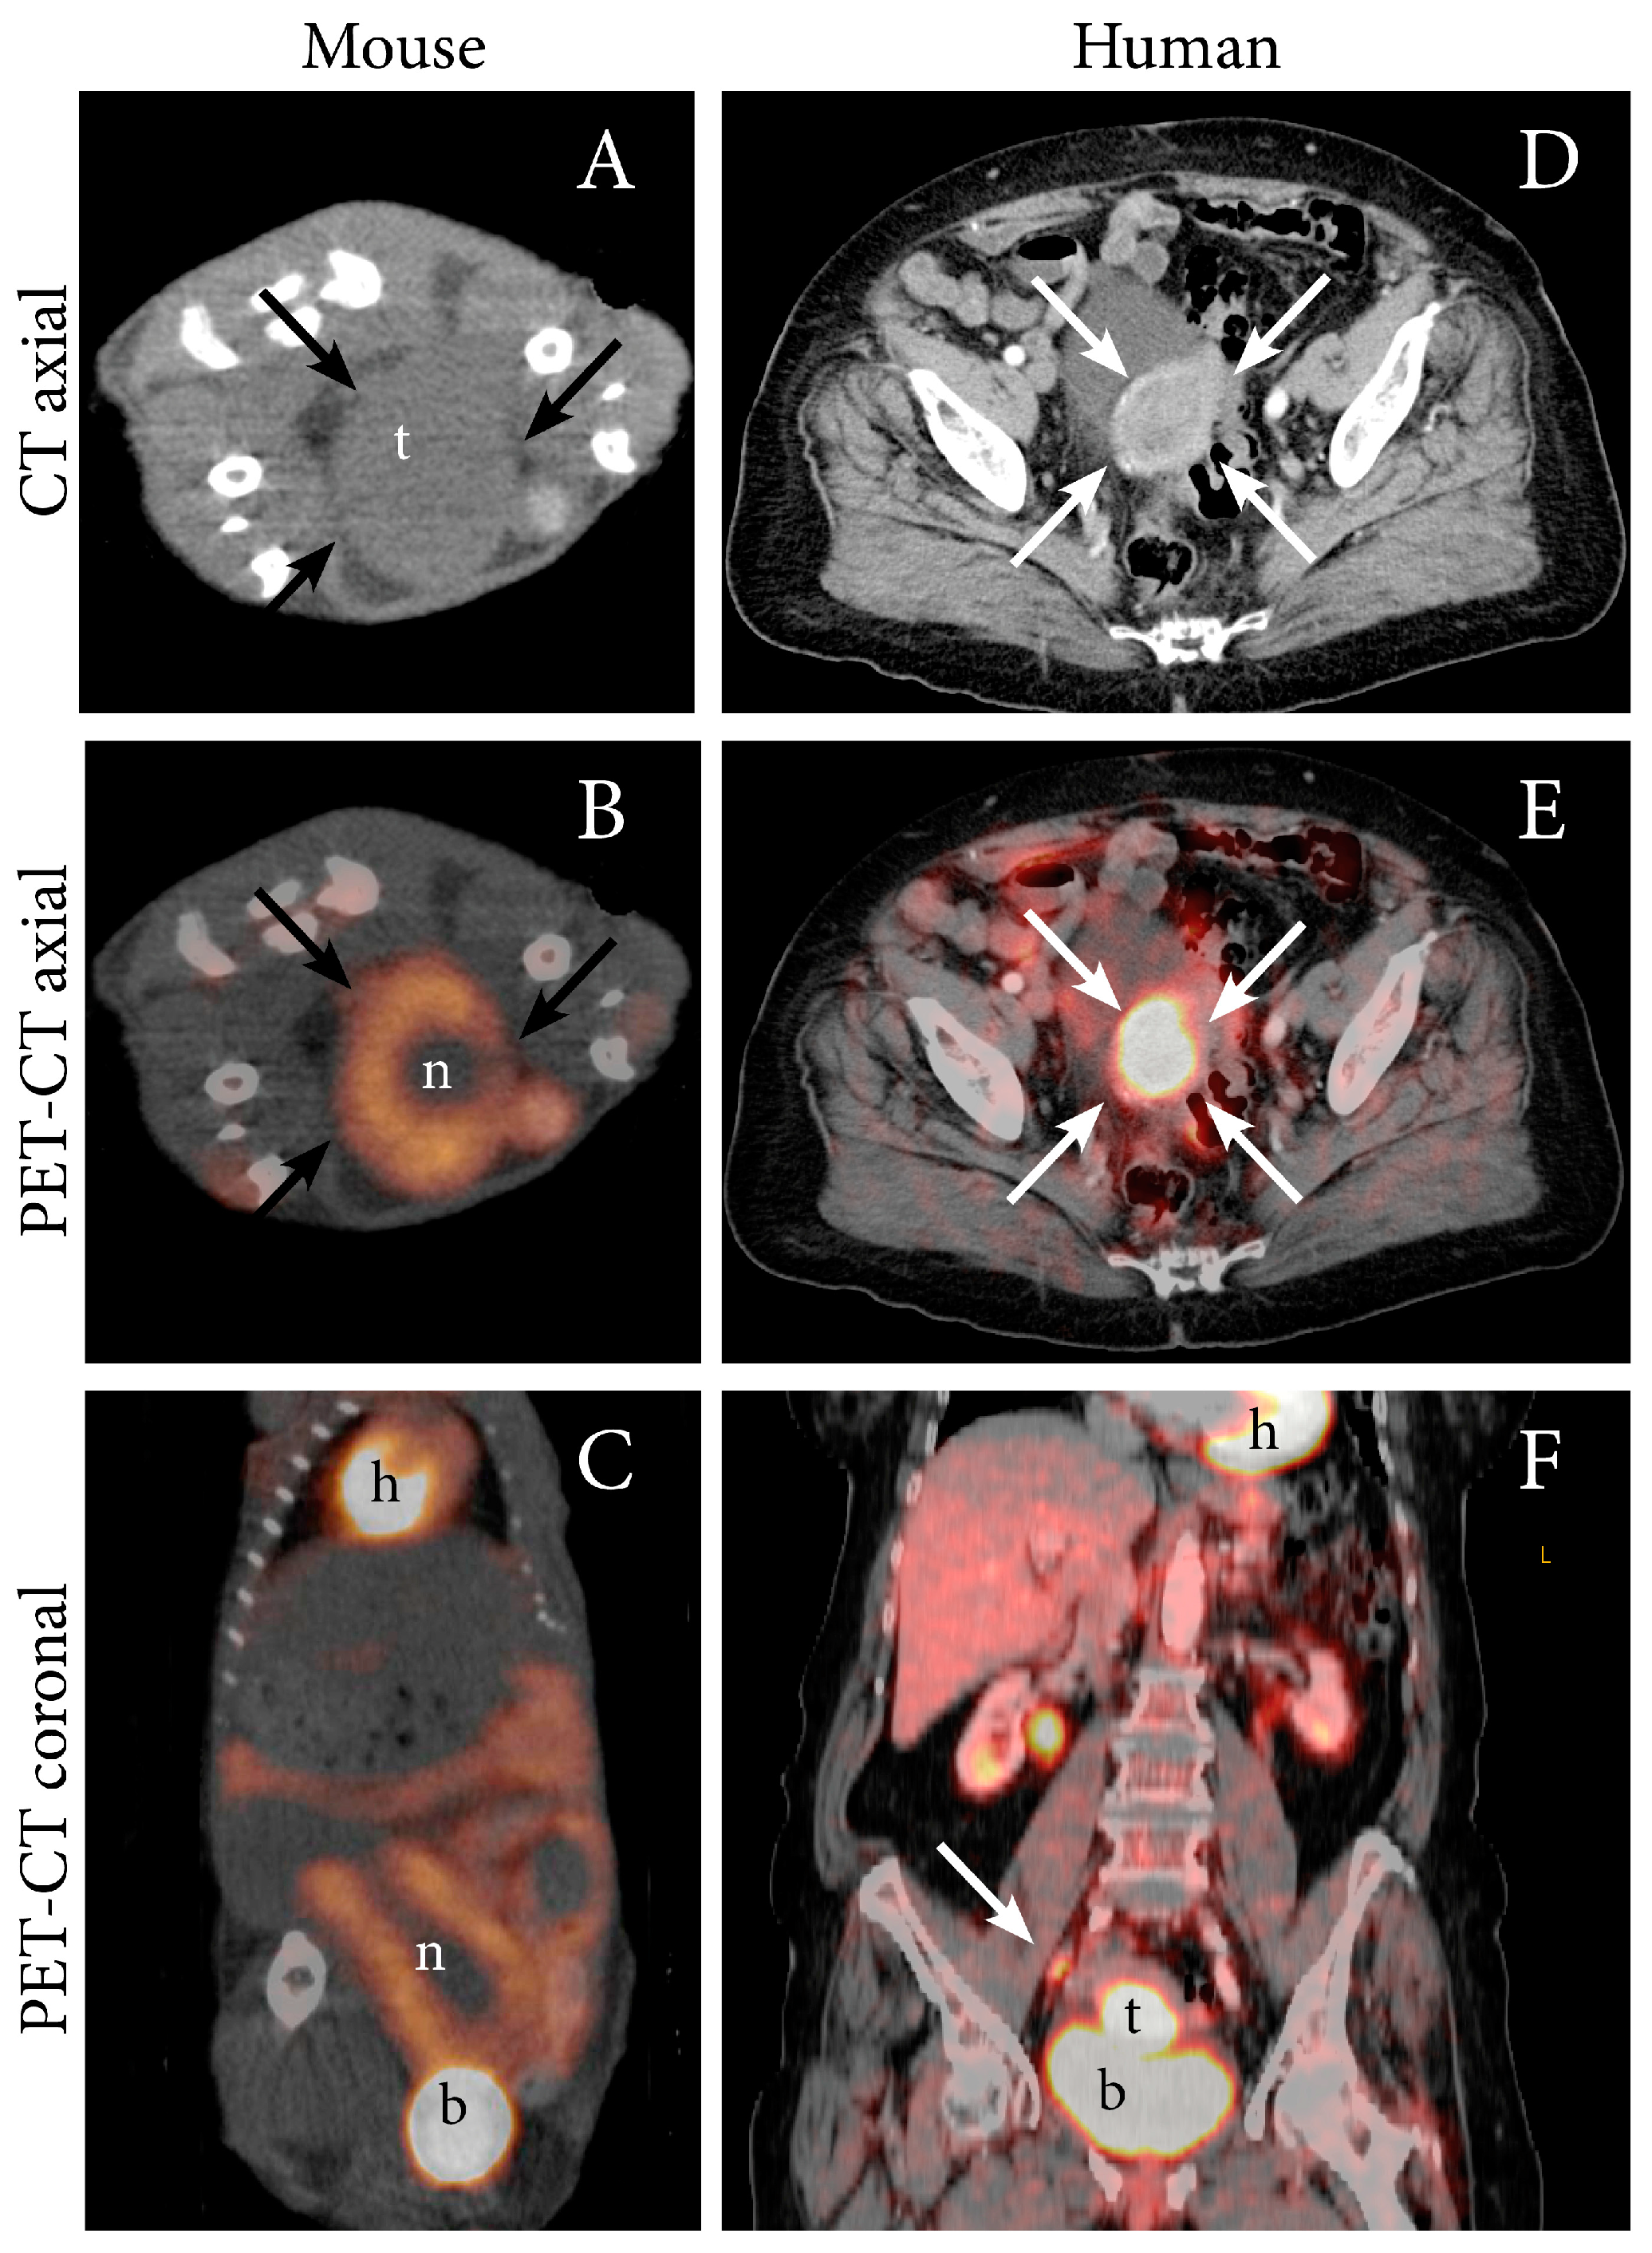

PET imaging in oncology is most often performed using the 18F-labeled glucose, fluorodeoxyglucose (FDG). Malignant cells are metabolically characterized by elevated energy demands and will normally have an increased uptake of glucose. Cancers will therefore typically exhibit high uptake of FDG generating contrast in PET images. PET-CT can detect lymph node metastases in EC with high accuracy, thus preoperative FDG-PET imaging is often recommended in high-risk EC [27,28]. In addition to elevated FDG uptake in metastatic lymph nodes, primary EC are also typically highly FDG avid [27]. Increased FDG uptake in an orthotopic tumor model from both Ishikawa cells and from human endometrioid grade 3 EC (PDX) has been demonstrated by our group using small-animal PET (Table 1) [12], and representative images illustrating the similar PET-CT findings observed in the PDX model and in human EC (endometroid grade 2, FIGO IIIC1) is shown in Figure 2.

Figure 2.

FDG PET-CT depicting an FDG-avid tumor in an orthotopic patient-derived xenograft (PDX) model of EC (grade 3 endometrioid) (A–C), and in an 87-year-old woman with EC (grade 2 endometroid, FIGO stage IIIC1; same patient as in Figure 1) (D–F). (A) In the mouse model, axial non-contrast CT imaging depicts a large tumor (t) (arrows) in the abdomen whereas (B) axial (C) and coronal FDG PET-CT display increased FDG uptake in the periphery of the tumor (arrows) and a central necrotic core (n). (D) In the patient, diagnostic contrast-enhanced axial CT image depicts a slightly enhancing primary tumor (arrows) and (E) axial and (F) coronal FDG PET-CT depict an FDG-avid primary uterine tumor (arrow) and a metastatic parailiac lymph node (arrow). Physiologic FDG uptake in the heart (h), liver, kidneys, renal pelvis and intestines and urinary FDG excretion to the bladder (b) is visible.